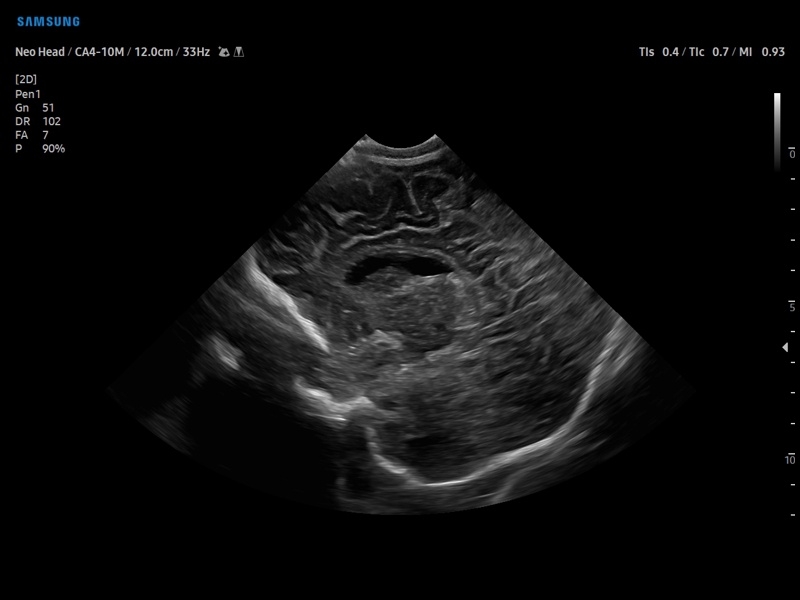

• Педиатрия и неонатология

• Транскраниальные исследования